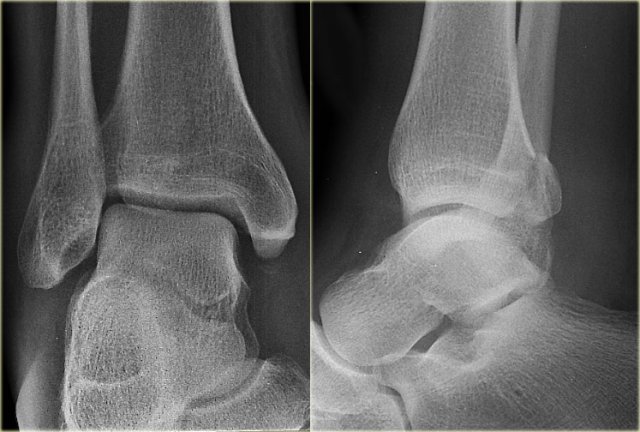

Weber B fracture Weber B fracture

The radiographs show a typical Weber B fracture.

First study the images and then continue reading.

Do you see what stage this is?

This is a Weber B stage 4 injury.

Notice that all 4 stages are visible:

1. Rupture of the anterior syndesmosis - seen as widening of the space between the distal tibia and fibula (lateral clear space).

2. Oblique fibula fracture at the level of the syndesmosis - i.e. Weber B fracture.

3. Tertius fracture - seen on AP view (red arrow) and on lateral view (yellow arrow).

4. Rupture of the medial collateral ligaments - seen as widening of the space between the medial malleolus and the talus (medial clear space)